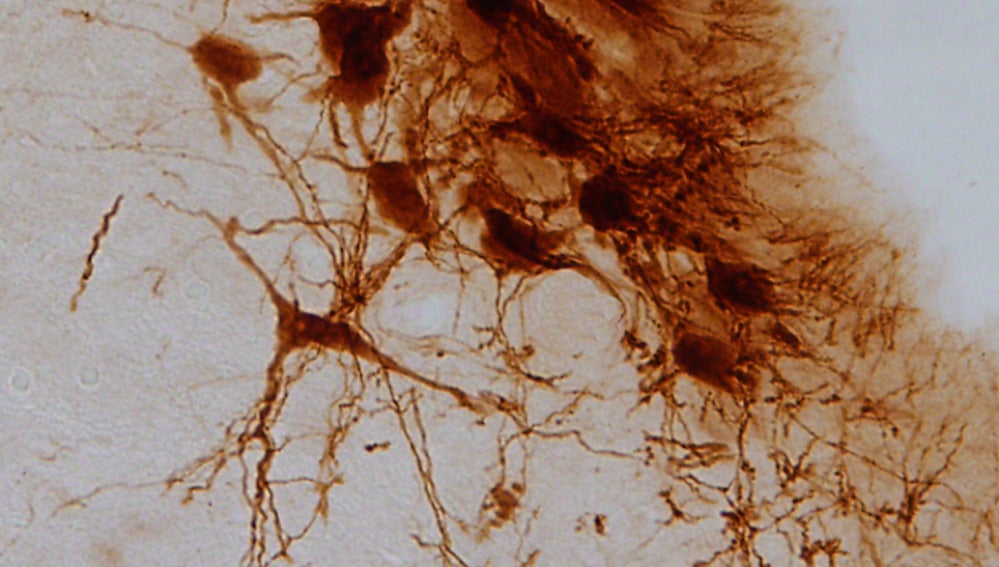

El locus cerúleo es el principal productor de noradrenalina del cerebro, una biomolécula involucrada en la transmisión del mensaje nervioso entre las neuronas y que desempeña un papel importante en la ansiedad y la depresión.

Sin embargo, este desarrollo se manifiesta en el cerebro mediante procesos diferentes. Cuando el dolor se origina por una diabetes mal controlada, este se refleja en el sistema nervioso central a través de una disminución en la producción de noradrenalina y una disfunción en la actividad del locus cerúleo, una región anatómica en el tallo cerebral involucrada en la respuesta al pánico y al estrés.

Por el contrario, cuando se trata de un dolor consecuencia de una lesión del nervio ciático, los investigadores observaron el efecto inverso: una hiperactividad del sistema noradrenergico.